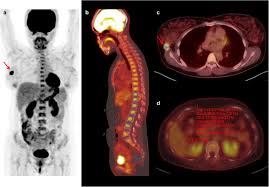

최첨단 현대의학으로 가장 적절한 방법이 양전자단층촬영술(Positron Emission Tomography, PET)이라고 나는 생각한다. PET는 체내 대사 변화를 촬영하는 기기로 CT나 MRI 다음에 개발된 영상장비이라고 한다.

요즘은 여기에 CT를 붙여서 PET 영상과 CT 영상을 융합해 서로 약점을 보완해 검사의 질을 더욱 높이고 있다고 한다.

여기에 방사성 핵종 F-18를 붙여(F-18 FDG라고 함) 혈관 주사하면 빨리 자리는 암세포는 포도당이 더 필요해 정상 세포보다 10∼100배 더 많이 모여들고 이를 방사능으로 촬영해 찾아낸다. 암이 1㎝만 돼도 10조개의 암세포가 있어 CT, MRI 소견이 애매한 경우 유용하게 쓰인다.

PET의 또 다른 장점으로 거의 모든 종류의 암을 찾아낼 수 있다는 것이라고 한다. 일반적으로 암세포는 포도당 대사가 높기 때문이라고 한다.

또 머리끝에서 발끝까지 촬영해 어느 곳에 있는 암이라도 잡아낸다. 다시 말하면 사각지대가 없다고나 할까? 이미 일본에서는 이 방법으로 암을 검진하는 프로젝트를 성황리에 진행하고 있다고 한다.